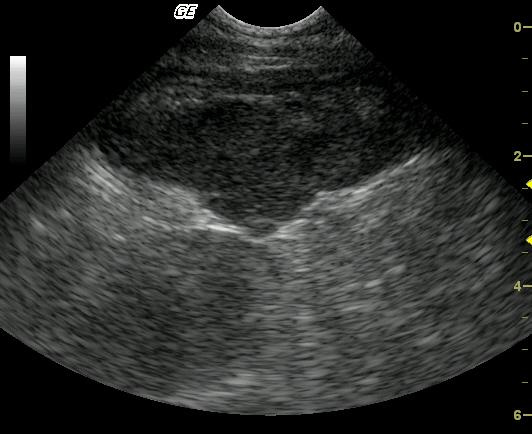

This 3-year-old MN DSH was presented for weight loss. The physical exam revealed hypothermia and palpably enlarged kidneys. A CBC and blood chemistry profile demonstrated severe azotemia that decreased after fluid therapy. Moderate anemia was also present.